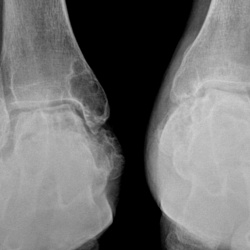

Здравствуйте, подскажите пожалуйста, как описать стопы? Пациент мужчина 40 лет, в анамнезе ревматоидный артрит

17.04.2024 - 17:50